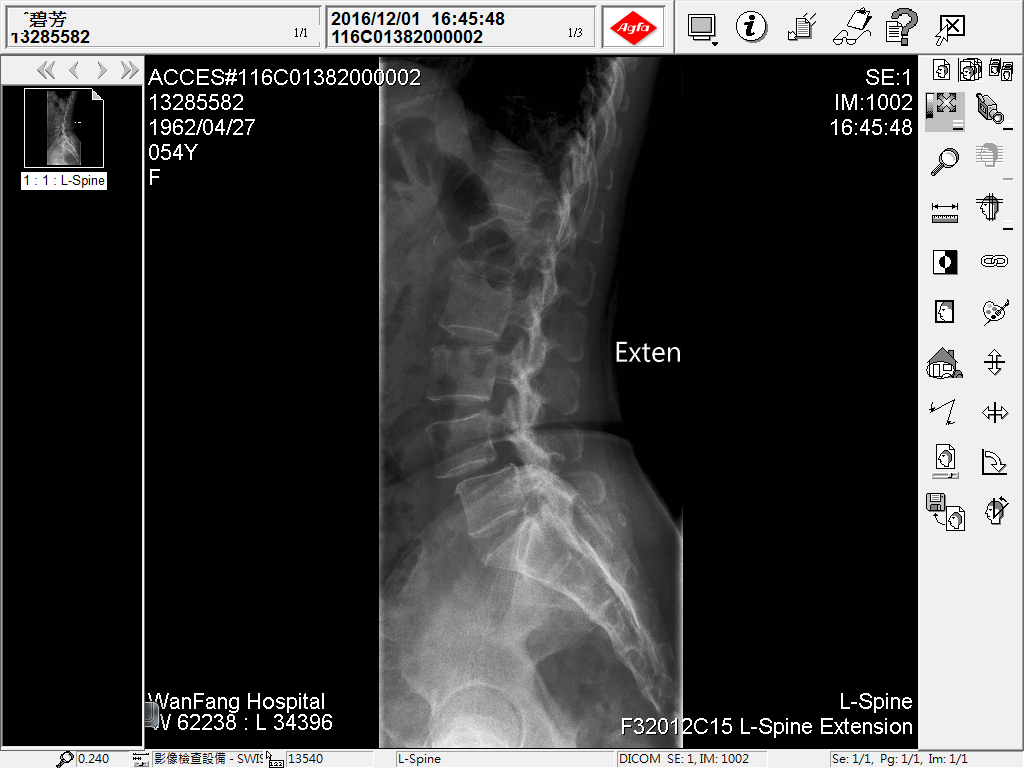

老先生家屬說他原本身體健壯,活動自如,但前兩年腰臀痛後檢查是腰椎滑脫,結果這兩年開了四次刀(包第一次括離譜的開錯部位的刀),結果,經歷四次開刀後,老先生又仍是腰腿痛麻,原本的疼痛沒有消失不說,幾次開刀後,腰上長達幾十公分刀疤,及腰椎上釘了18支鋼釘,讓老人家每天都痛不欲生,老先生家屬束手無策,卻又不知如何解決問題。

第一慘,兩年前他腰痛,腰椎滑脫!

第二慘,他兩年來在大醫院開四次刀,這四次還包括第一次開錯刀(患者家屬自訴開錯部位),在某大醫院開了三次刀問題加劇,甚至到最後還找不到醫師肯接手開刀,結果總共開了四次刀,還沒解決問題難當

第三慘,第四次開刀完成,打了18支鋼釘,背後刀疤數十公分,鎮日疼痛,